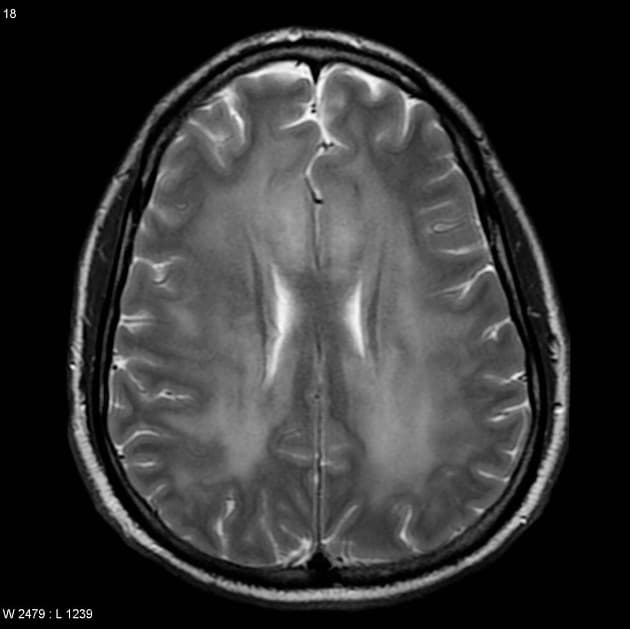

Chụp cộng hưởng từ (MRI) cho thấy các đặc điểm điển hình của bệnh xơ cứng rải rác. Ngoài ra, một số tổn thương có tín hiệu tăng trên hình ảnh T1 (T1 hyperintense).

- Các tổn thương rải rác, dạng vệt hoặc hình tròn, tăng tín hiệu trên hình ảnh khuếch tán (diffusion-weighted imaging), khu trú chủ yếu ở vùng chất trắng quanh thất (periventricular white matter), chất trắng ở bán nguyệt (juxtacortical white matter), thân gai thị – giao thoa thị giác (optic radiation – optic chiasm), và thân não (brainstem) – phù hợp với đặc điểm của xơ cứng rải rác (multiple sclerosis).

- Một số tổn thương có tín hiệu tăng trên T1 (T1 hyperintense lesions) – gợi ý tổn thương mạn tính, liên quan đến mức độ tàn phế tăng và teo não (atrophy).

- Thể chai (corpus callosum) có tổn thương dạng dải ngang (Dawson's fingers) – đặc trưng của xơ cứng rải rác (multiple sclerosis).

- Không có tổn thương màng não (leptomeningeal) hay ngấm thuốc viền (rim enhancement).

- Các não thất và khe não bình thường về kích thước, không thấy giãn não thất (hydrocephalus) hay xóa (rãnh não/bể não) (effacement).

- "Dawson's fingers là các tổn thương ở chất trắng quanh thất, định hướng vuông góc với não thất, đặc trưng cho xơ cứng rải rác."